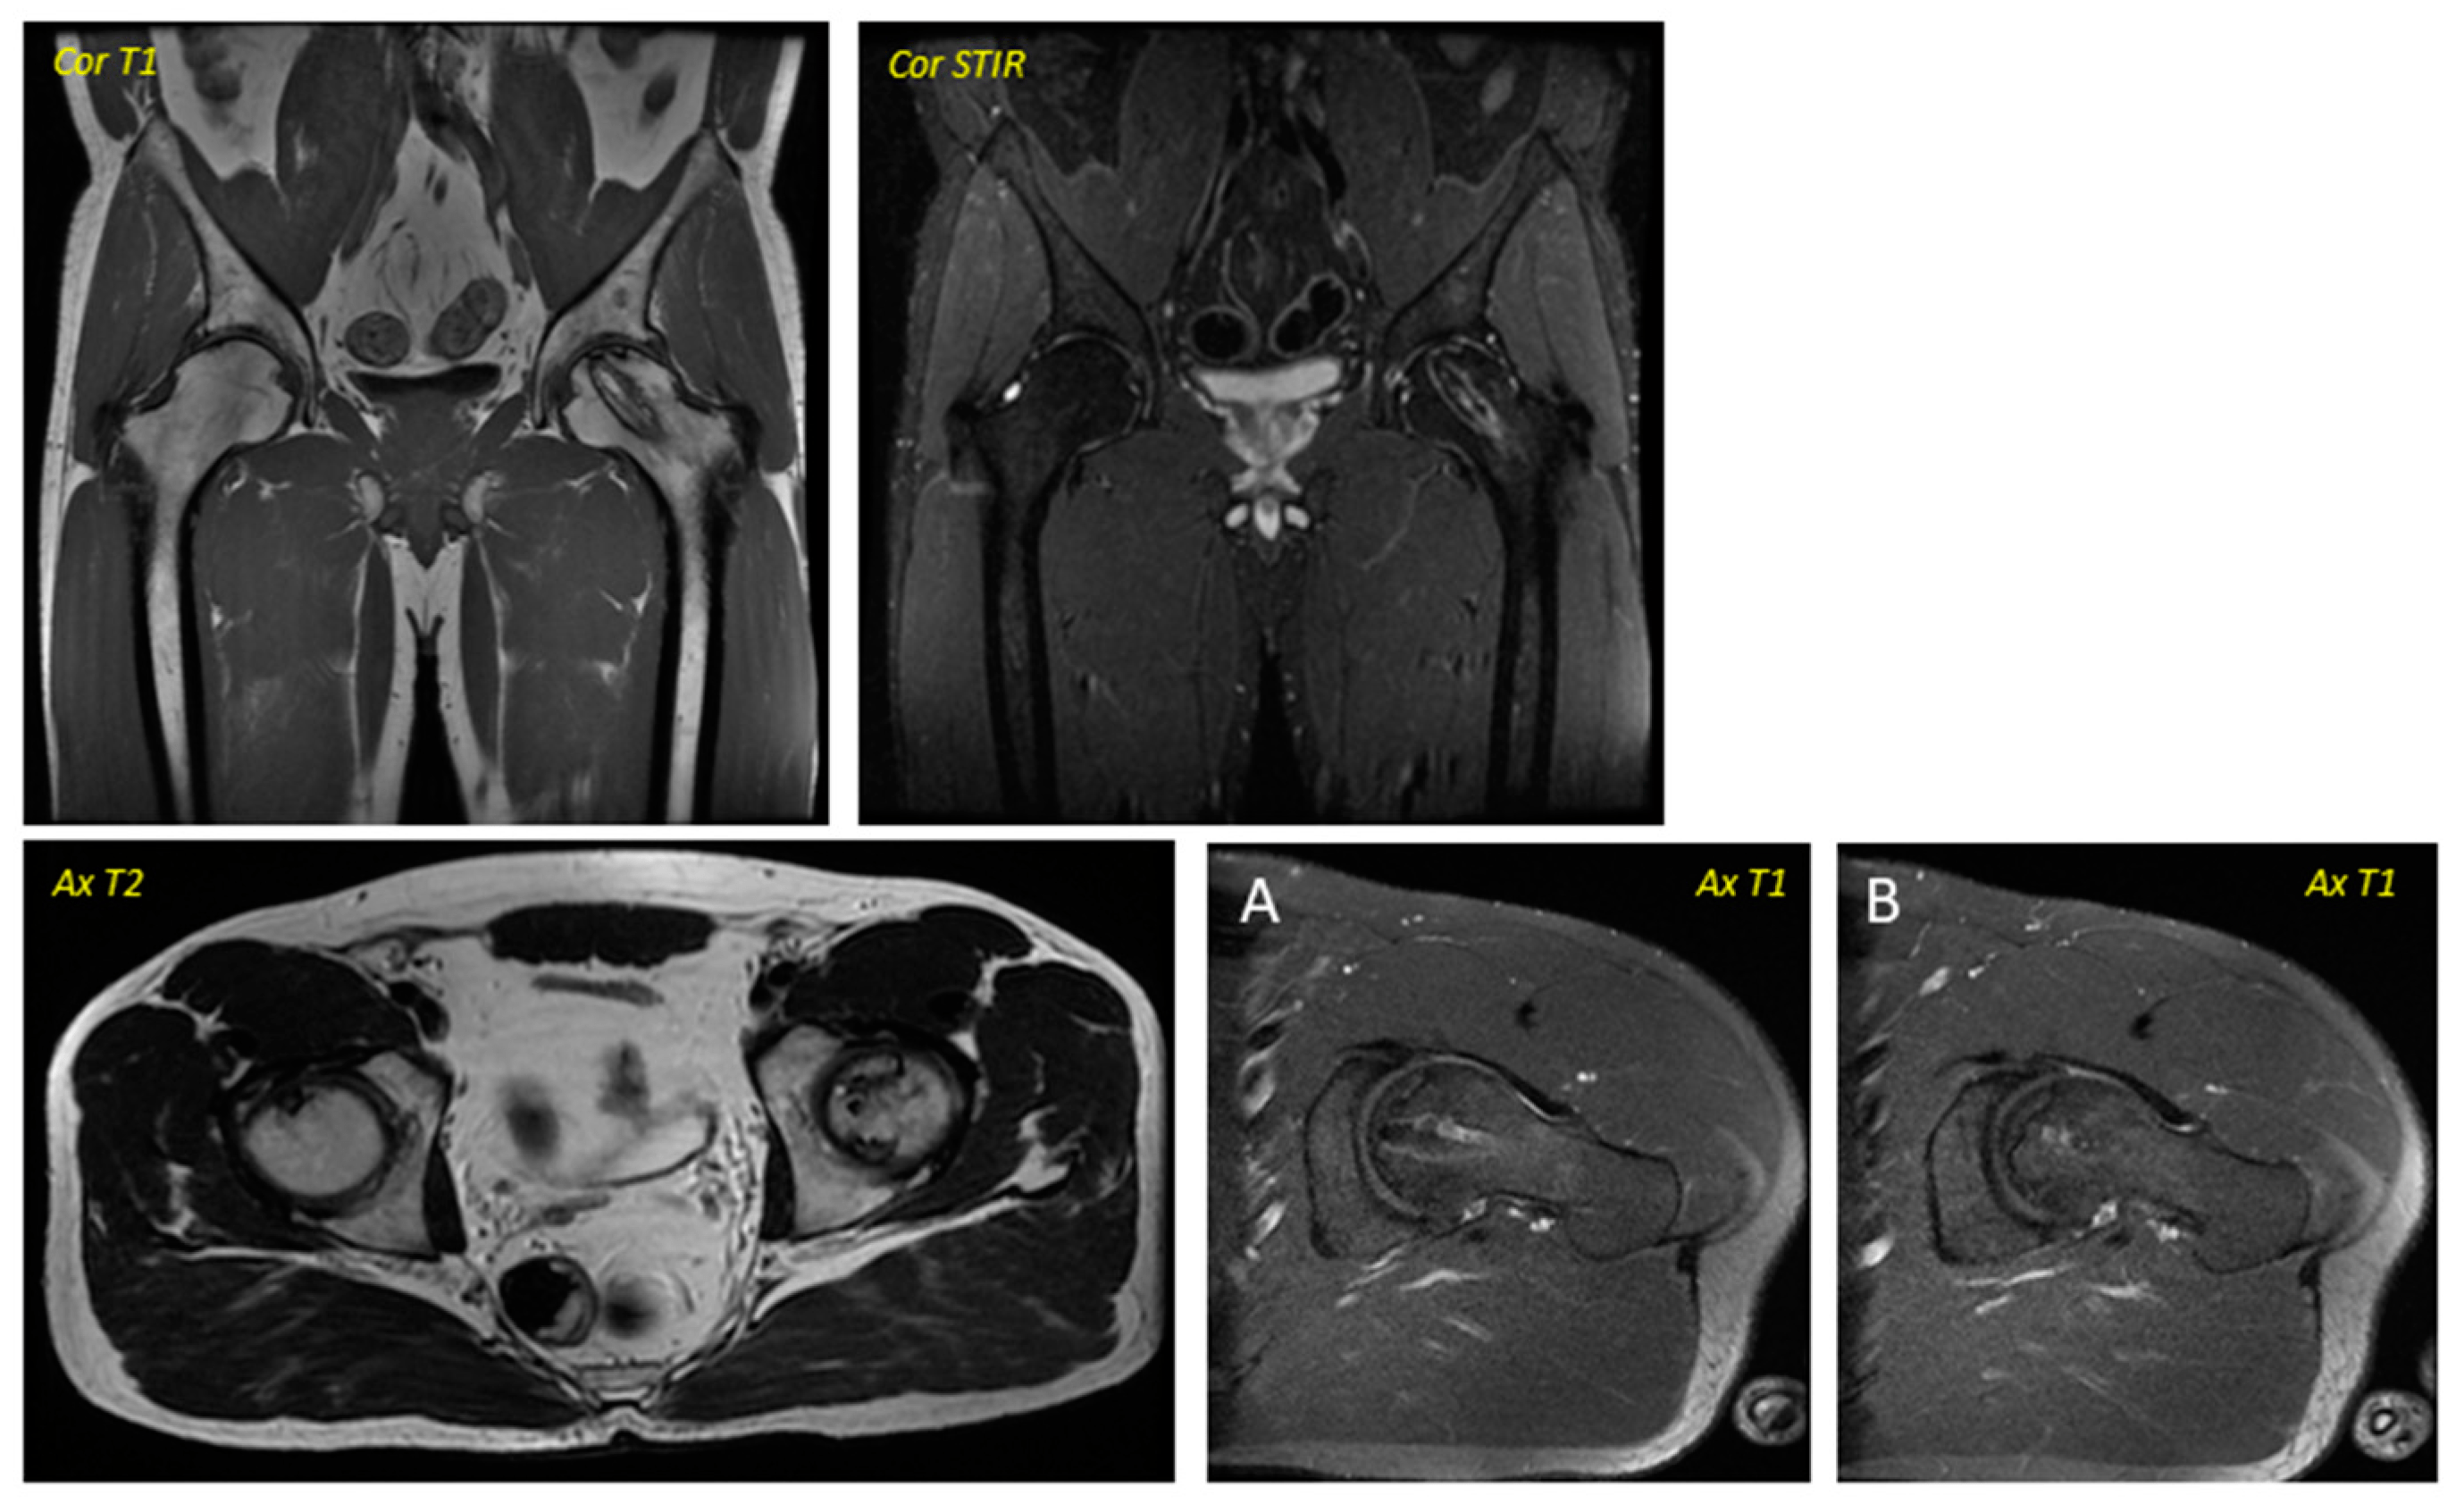

關(guān)于影像學(xué)研究,在12個(gè)月的隨訪(fǎng)期間,在影像學(xué)演變中觀(guān)察到了一些發(fā)現(圖1和圖2)。

首先,方向的變化從第六個(gè)月開(kāi)始出現在所有病例中,而在早期階段并不明顯。其次,62.5%的患者 ( n=5) 在手術(shù)后的第一年內實(shí)現了影像穩定。第三,兩名患者 (25%) 出現壞死區進(jìn)展,而一名 (12.5%) 患者出現明顯的再骨化跡象。盡管觀(guān)察到描述性差異,但后一個(gè)參數的p值在統計學(xué)上并不顯著(zhù)。

圖1:對應于2013年12月執行的一名38歲男性的術(shù)前圖像